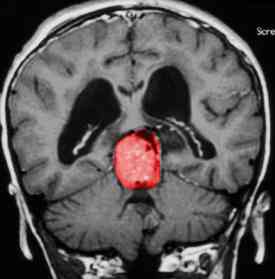

PINEAL CYSTS

Benign cysts of the pineal gland are often found incidentally on radiographic studies, and it is important to distinguish them from cystic tumors. They are normal variants of the pineal gland and consist of a cystic structure surrounded by normal pineal parenchymal tissue. Radiographically they are up to 2 cm in diameter and often have some degree of peripheral enhancement that may be a compressed normal pineal gland. Pineal cysts may be found in 4% of all magnetic resonance images. These cysts are static anatomic variants and need no treatment unless they become symptomatic. In one series of 53 pineal cysts, fewer than 10% developed hydrocephalus requiring surgical intervention.